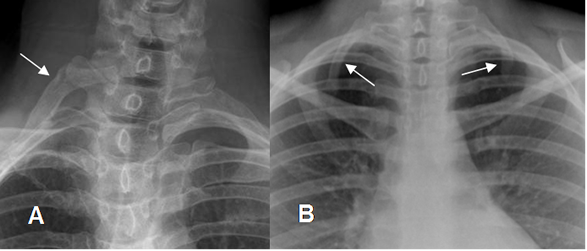

Fig 21. Costilla cervical.

A y B: Rx AP. Costillas supernumerarias, en relación con la apófisis transversa de C7. En la malformación es bilateral.